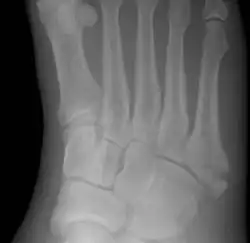

Jones fracture

![]() | |

| Jones fracture as seen on Xray | |

A Jones fracture is a broken bone in a specific part of the fifth metatarsal of the foot between the base and middle part .[8] In general, fifth metatarsal fractures heal readily, but a Jones fracture must be recognized and accurately diagnosed because of its higher rate of delayed healing or nonunion.[4] It results in pain near the midportion of the foot on the outside.[2] There may also be bruising and difficulty walking.[3] Onset is generally sudden.[4]

The fracture typically occurs when the toes are pointed and the foot bends inwards.[6][2] This movement may occur when changing direction while the heel is off the ground such in dancing, tennis, or basketball.[9][10] Diagnosis is generally suspected based on symptoms and confirmed with X-rays.[3]

Diagnostic X-rays include anteroposterior, oblique, and lateral views and should be made with the foot in full flexion.